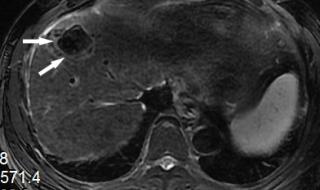

原发性肝癌,又叫肝癌,是肝脏细胞或肝内胆管上皮细胞发现的恶性肿瘤。肝脏发现肿瘤,可以是肝脏本身产生的,也可以是其他部位转移而来的。如果比如胃癌转移到肝脏,叫胃癌肝转移。原发性肝癌在我们最常见的是慢性肝炎导致肝硬化,发展成原发性肝癌。

原发性肝癌发展到了晚期的话会出现一些恶液质状态,比如患者的肚子会出现非常鼓的现象,并且伴随有腹胀的感觉,还会出现黄疸的现象,体质状况会越来越虚弱,这个时候的治疗主要是是保守治疗为主,还有进行化疗或者是介入治疗等综合治疗的措施。